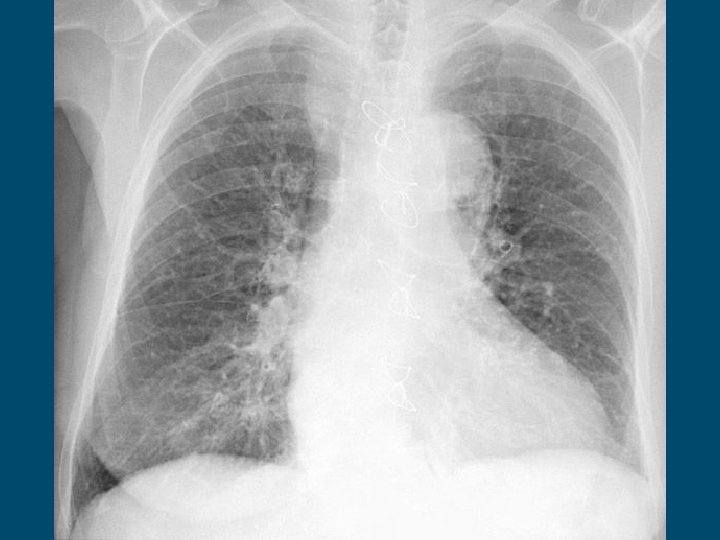

Lung Cancer § Can also be classified as carcinoma (aggressive). § Typically no immediate symptoms. § May have severe cough, wheezing, coughing up blood, and hoarseness. § It is detected in a chest x-ray. § Behavioral factors – smoking, general air pollution § Environmental factors – exposure to radon, asbestos